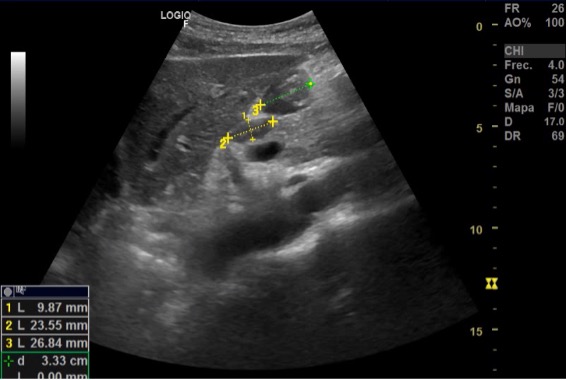

Ecografía: Conglomerado adenopático en axila izquierda. Adenopatía más grande (30 x 40 mm) hipoecogénica, redonda con pérdida del hilio graso, de aspecto infiltrativo y con captación Doppler. Adenopatías infraclaviculares de 27,5 x 12,2 y una glomerulación de 13,9 x 17,1 mm hipoecogénicas con pérdida de estructura normal. Adenopatías perihiliares hepáticas de 9 x 23 mm y otro 26 x 17; perihiliar esplénica de 12 x 4 x 5 mm, e inguinal izquierda de 9,3 x 7,8 mm.